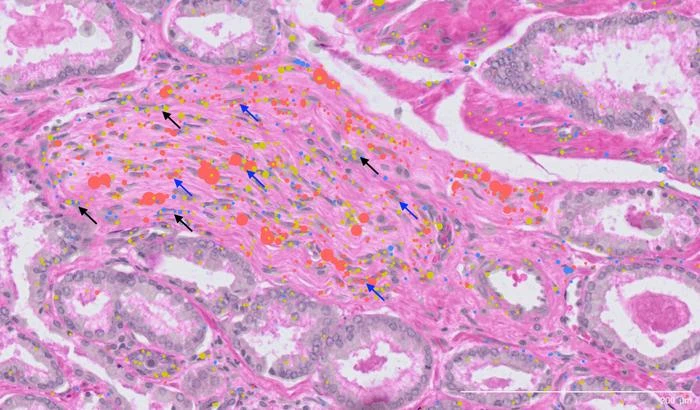

The research team, led by Professor Alexander Swarbrick, Co-Director of the Cancer Ecosystems Program and Lab Head at Garvan, analysed tissue from 24 patients recently diagnosed with early-stage prostate cancer. The samples were drawn from the Garvan St Vincent’s Prostate Cancer Biobank – the largest in the southern hemisphere, with contributions from more than 16,000 patients over three decades. The team then used advanced single-cell RNA sequencing to examine the genetic activity of every single cell in a tissue, and spatial transcriptomics to map their exact locations in the tumour landscape.

This resulted in a comprehensive atlas, identifying 11 major cell types, 50 minor subtypes, and numerous cell state classifications within prostate cancer tissue. This level of detail provides the global research community with an invaluable resource for studying how the tumours form and opportunities to design new therapeutics.

Standard diagnosis relies on visually identifying structural irregularities in cells under a microscope. However, this study revealed that the progression from healthy prostate tissue to cancer involves multiple cellular states that are invisible. The researchers found that many epithelial cells – the cells that line organs and are where most cancers originate – showed early genomic alterations, even in tissue that appeared ‘normal’. This suggests that molecular testing could one day be used to detect these invisible warning signs, potentially allowing for diagnosis before the cancer can be seen by a pathologist.

Among the study’s most significant findings is the identification of a previously unknown cell type – called perineural cancer-associated fibroblasts, a type of connective tissue cell located near nerves in cancers.

The tendency for tumours to grow in and around nerves in prostate cancer has long been associated with worse patient outcomes. This discovery of specialised cells that interact with these nerves provides a new piece of the puzzle in understanding how prostate tumours may recruit nerves, or spread to other parts of the body along the nerves to cause metastatic disease.